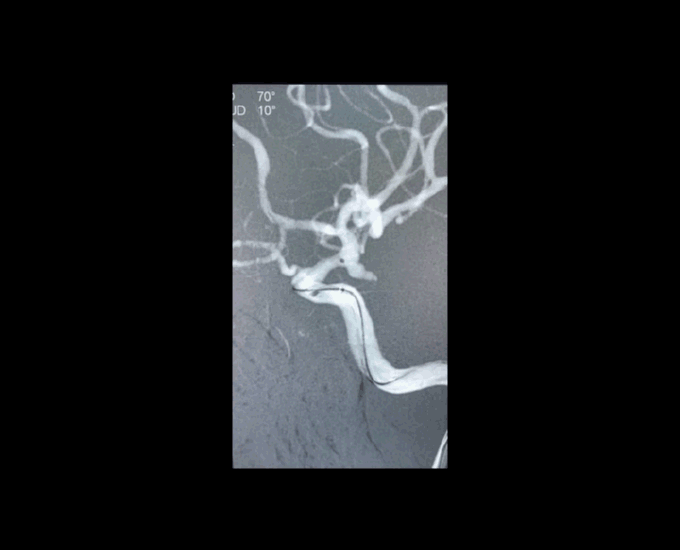

大C塑形

10mm以上的大动脉瘤:

(1)C型头端完全进入动脉瘤囊内,微导管的盘旋有利于均匀填塞

(2)避免微导管头端过早踢出

病例一